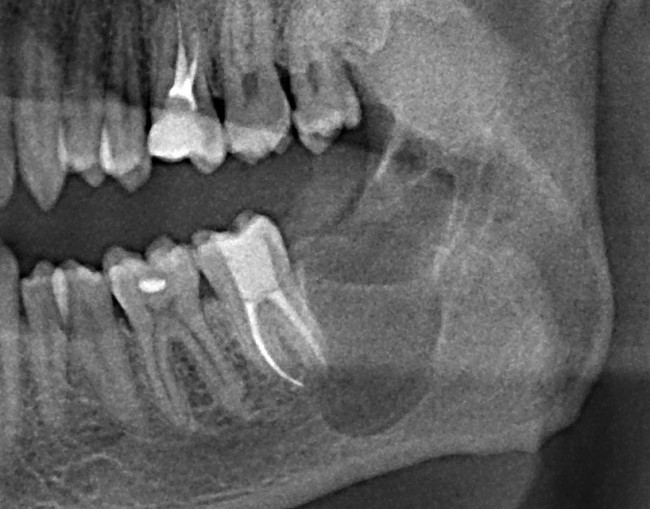

Что мы и делаем. До удаления я попросил нашего терапевта Михайлову Елену депульпировать соседний седьмой зуб, поскольку, по данным КЛКТ, его корни выходили в просвет кисты. Жалко, конечно. Но вот, такие коварные эти зубы мудрости.

Итак, удаляем зуб и кисту.

Это занимает, в общей сложности, около получаса: 10 минут на удаление зуба, еще 15 минут на удаление кисты и наложение швов.

Представьте себе — 30 минут. И все. Нет никаких угроз здоровью.